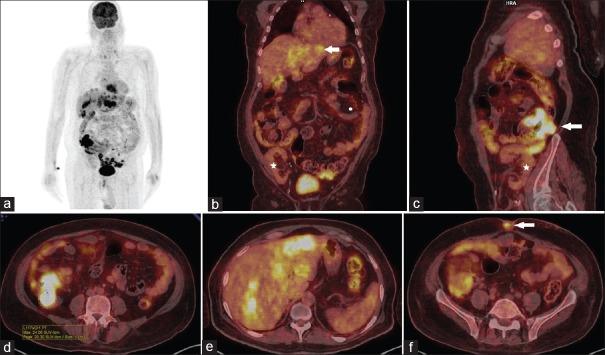

肾移植后转移性结肠肿瘤:移植后淋巴细胞增殖性疾病还是腺癌?

Postrenal Transplant Metastatic Colonic Neoplasm: Posttransplant Lymphoproliferative Disorder or Adenocarcinoma?

Transplant recipients are vulnerable to a horde of infections and neoplastic conditions due to immunosuppression. Posttransplant lymphoproliferative disorder (PTLD) is a condition unique to the transplant recipient occurring due to monoclonal lymphocytic proliferation. It may affect any organ system with reportedly highest incidence in the gastrointestinal tract. The incidence of adenocarcinoma of the colon, however, has not been shown to be uniformly higher in transplant recipients. We report here an unusual case of adenocarcinoma of the ascending colon presenting with liver, lymph node and skin metastasis in a transplant recipient, which simulated PTLD both clinically and radiologically. For any gastrointestinal lesion in transplant recipient, the possibility of carcinoma must be considered. However, a high index of suspicion for PTLD facilitates early diagnosis since the treatment of the two conditions is starkly different.

摘要

由于免疫抑制,移植受者易受多种感染和肿瘤性疾病的影响。移植后淋巴增殖性疾病(PTLD)是移植受者特有的一种疾病,由单克隆淋巴细胞增殖引起。它可累及任何器官系统,据报道在胃肠道的发病率最高。然而,结肠腺癌的发病率在移植受者中并未显示出普遍更高。我们在此报告一例升结肠癌的罕见病例,该病例在一名移植受者中出现肝脏、淋巴结和皮肤转移,在临床和放射学上均类似于PTLD。对于移植受者的任何胃肠道病变,必须考虑癌的可能性。然而,对PTLD高度怀疑有助于早期诊断,因为这两种疾病的治疗截然不同。